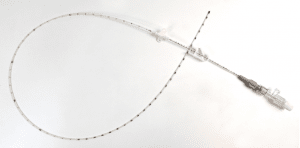

Sin embargo la selección del dispositivo puede deberse a veces a la escasa información que define las indicaciones apropiadas para el uso del PICC de una sola luz (Figura 1) frente al multilumen14 .

Los PICC de doble y triple luz (Figura 2) se asocian con un aumento de las oclusiones. Dependiendo de la situación clínica, deben preferirse los lúmenes individuales tal y como apuntan las guías de práctica clínica16-19